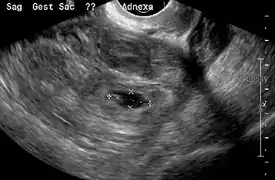

An ultrasound showing a gestational sac with fetal heart in the fallopian tube has a very high specificity of ectopic pregnancy. Transvaginal ultrasonography has a sensitivity of at least 90% for ectopic pregnancy.[4] The diagnostic ultrasonographic finding in ectopic pregnancy is an adnexal mass that moves separately from the ovary. In around 60% of cases, it is an inhomogeneous or a noncystic adnexal mass sometimes known as the "blob sign". It is generally spherical, but a more tubular appearance may be seen in case of hematosalpinx. This sign has been estimated to have a sensitivity of 84% and specificity of 99% in diagnosing ectopic pregnancy.[4] In the study estimating these values, the blob sign had a positive predictive value of 96% and a negative predictive value of 95%.[4] The visualization of an empty extrauterine gestational sac is sometimes known as the "bagel sign", and is present in around 20% of cases.[4] In another 20% of cases, there is visualization of a gestational sac containing a yolk sac or an embryo.[4] Ectopic pregnancies where there is visualization of cardiac activity are sometimes termed "viable ectopic".[4]

Ultrasound image showing an ectopic pregnancy where a gestational sac and fetus has been formed.

The combination of a positive pregnancy test and the presence of what appears to be a normal intrauterine pregnancy does not exclude an ectopic pregnancy, since there may be either a heterotopic pregnancy or a "pseudosac", which is a collection of within the endometrial cavity that may be seen in up to 20% of women.[4]